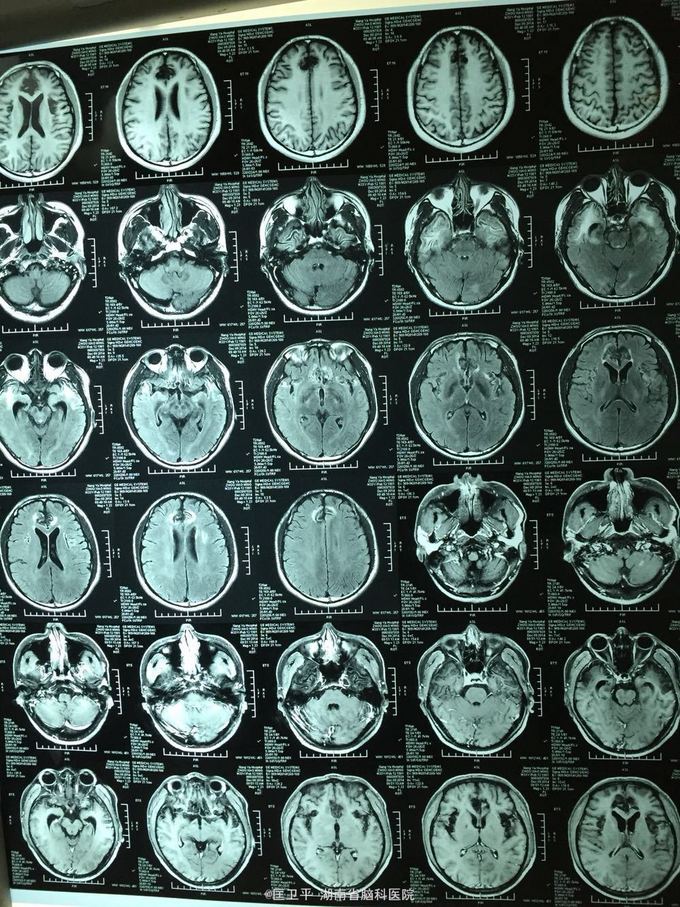

电击伤后智力低下,伤人毁物1年。 一年前在工地被电击伤昏迷,心跳呼吸停止,十几分钟后才有不规范的人工呼吸,持续约40分钟,心跳呼吸恢复。但患者智力低下,远近记忆很差,疑人害,伤人毁物严重,无法管理。

神清欠合作,五官无畸形,四肢活动正常,无神经定位体征。智能记忆很差,有被害妄想,有冲动攻击行为,无自知力,个人生活无法自理。